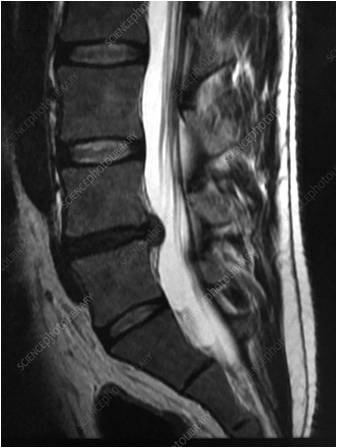

- Κήλη μεσοσπονδυλίου δίσκου

- Στένωση σπονδυλικού καναλιού

- Εκφυλιστική σπονδυλοαρθρίτιδα, τρηματική στένωση στο σημείο εξόδου της ρίζας

- Σπονδυλολίσθηση